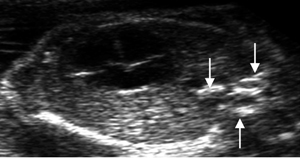

Εικόνα 20. Διάταση κοιλιών σε στεφανιαία τομή. Εικόνα 21. Οπίσθια κέρατα κοιλιών δίκην (teardrops) και απουσία διαφανούς διαφράγματος (μεγάλο βέλος).